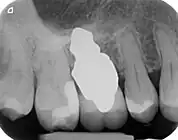

A root analogue implant can be fabricated from zirconium dioxide (zirconia) or titanium. Successful titanium RAIs have been three-dimensionally printed as porous one-piece implants, using CAD software.[4] However, zirconia is the preferred material, because it is more esthetic in colour, with no grey discolouration visible through gums.[5][1]

- Esthetic: a ceramic RAI closely resembles a natural tooth in colour. Thus there is no discolouration through the gums, as is commonly seen with titanium implants.

A new attempt was made by Pirker et al 2004 in a human trial with root analogue zirconia implants, but this time by applying differentiated osseoingration on the surface. In 2011 he reported 90% success rate with this method in a 2.5 year human trial.[11]

There is increasing concern in implantology about esthetics, biocompatibility, and the corrosive behaviour of materials.[1][8] While custom root analogue zirconia implants offer significant benefits over conventional titanium implants, and follow-up studies with patients show high success rates and satisfactory esthetic results,[1][13][15] further studies are needed to evaluate surface-bone interactions and mechanical behaviour of zirconia.[8][13][14]